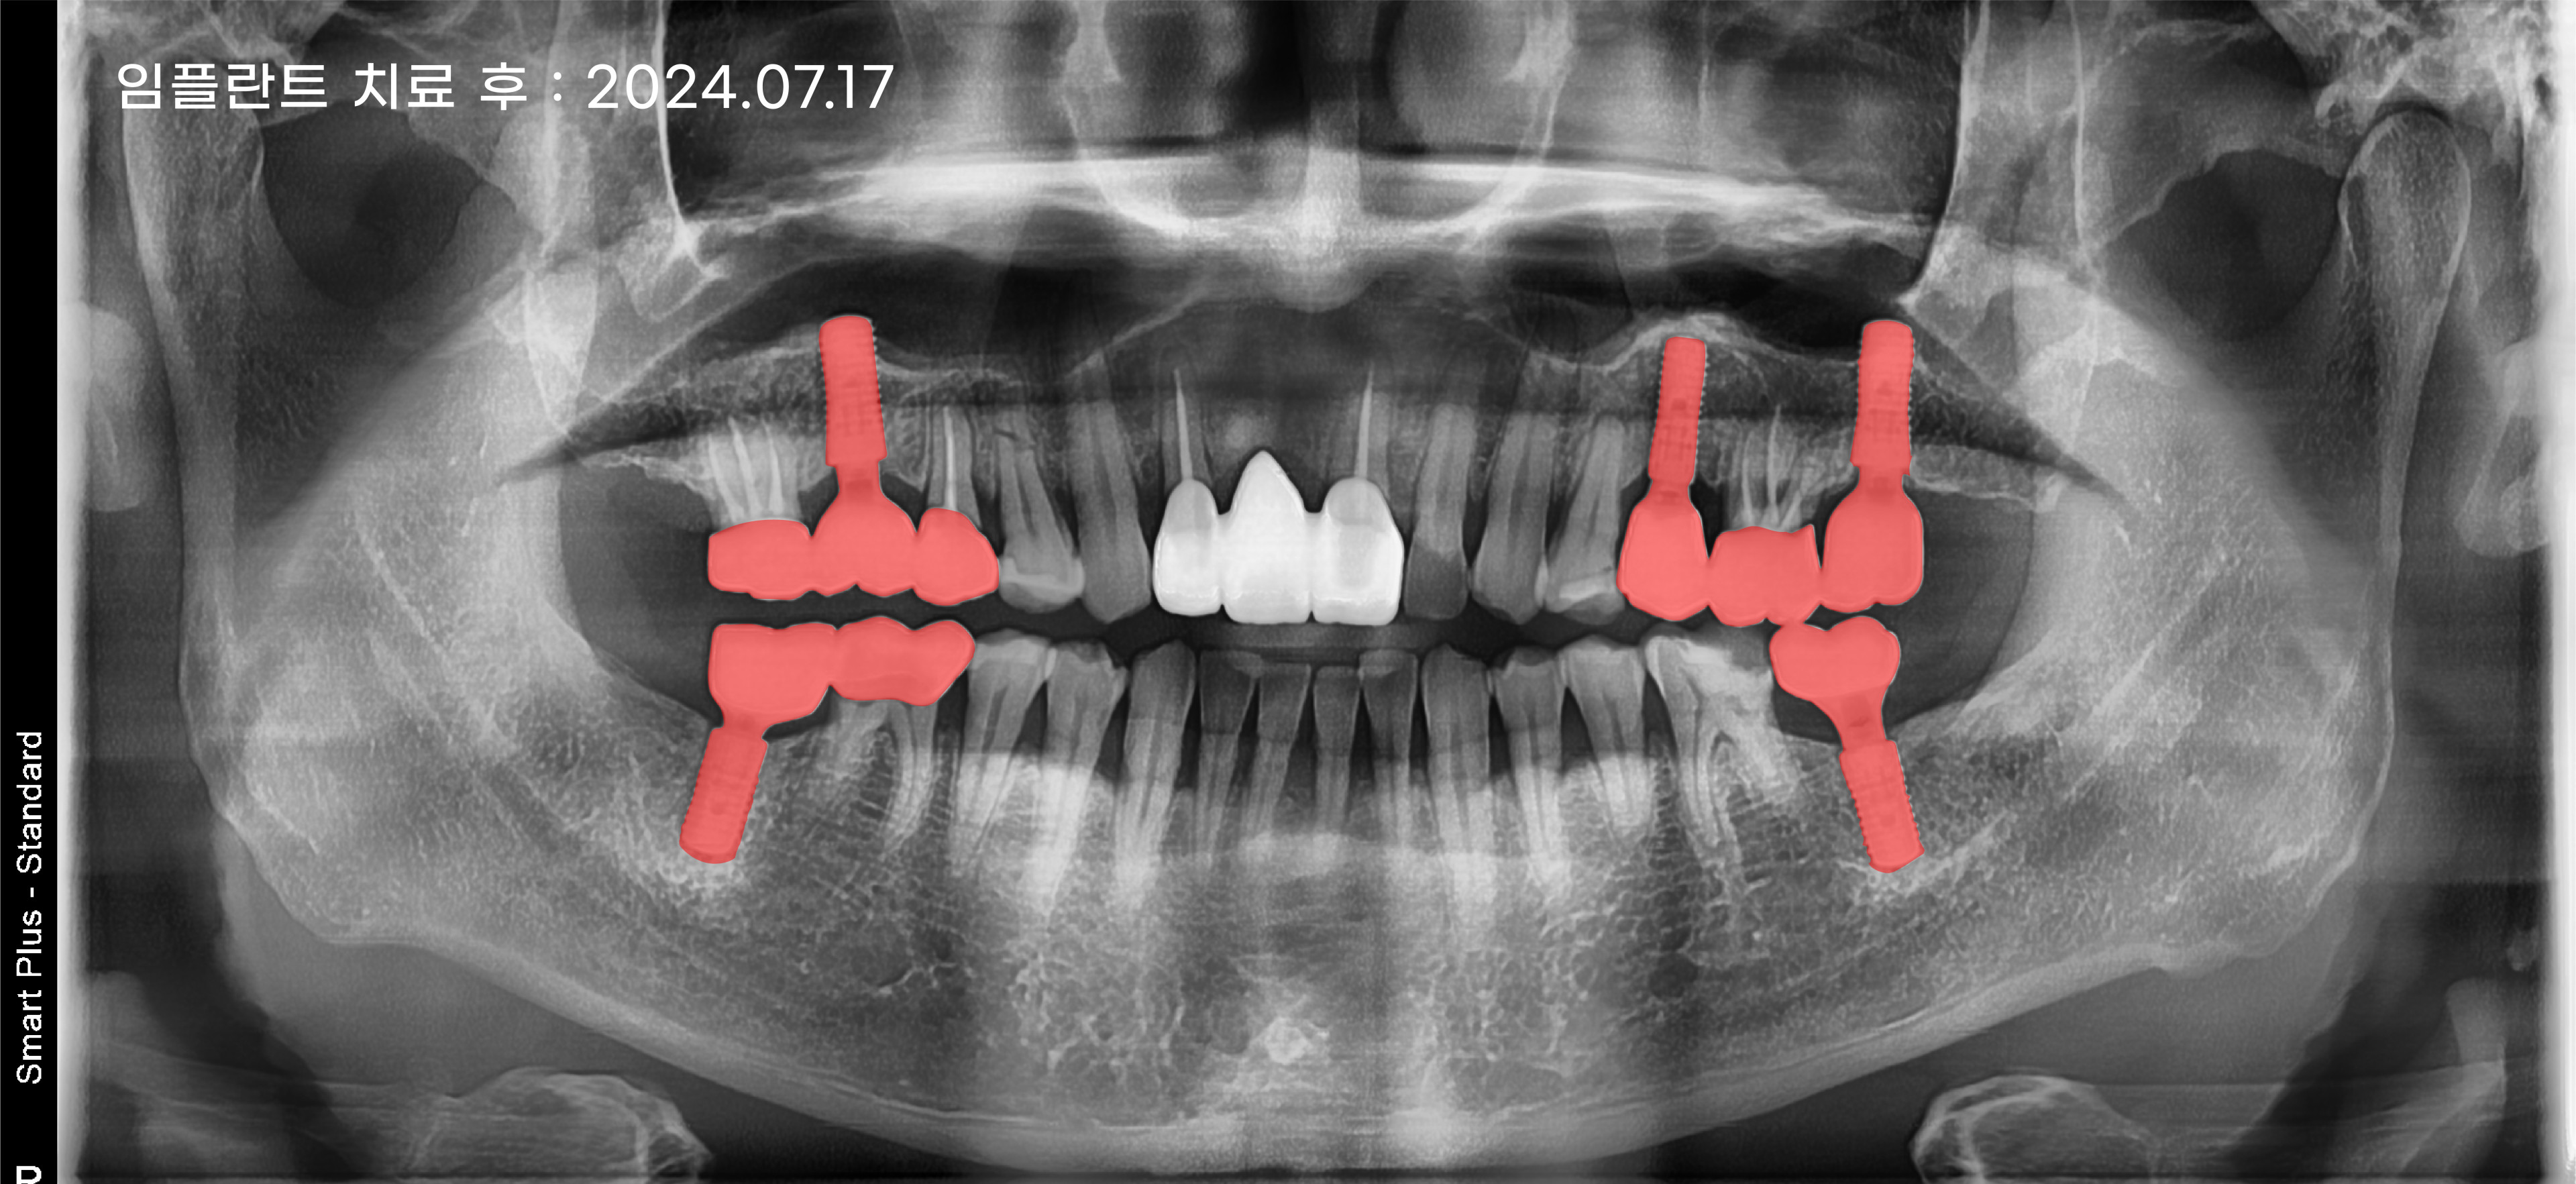

어금니 임플란트는 턱뼈에는 있는 신경을 손상시키지 않고 안전하게 임플란트를 식립해야 합니다.

그리고 위아래 치아 교합 또한 중요한데요.

교합이 맞지 않으면 저작 기능을 제대로 하지 못할 뿐만 아니라 턱관절에도 악영향을 줄 수 있으며,

주변 치아와 잇몸에도 부정적인 영향을 줄 수 있습니다.

구강 구조는 사람마다 다르며 똑같은 사람은 없기 때문에 잇몸의 모양, 치아의 크기, 그리고 아래위 치아의 교합까지

고려하여 해운대임플란트치과 세종치과는 개개인에게 꼭 맞는 임플란트를 심어 드리고 있습니다.

의료진의 실력을 뒷받침해 줄 첨단 장비와 체계적인 시스템으로 면밀하게 진단하고 정확한 위치와

각도 그리고 교합 등 세밀한 치료 계획을 세워 안정적인 수술 결과를 만들어 내고 있습니다.